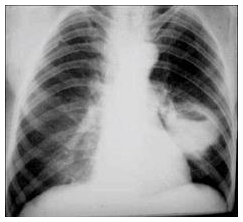

Um homem de 36 anos procura o pronto-socorro com queixa de febre baixa, tosse produtiva e perda de peso há 3 semanas. Trabalha na zona rural como cortador de cana, é tabagista e “bebe socialmente”. Tem epilepsia desde a infância e nos últimos 3 meses tem apresentado convulsões por ter abandonado o tratamento. A radiografia de tórax mostra:

O diagnóstico mais provável é